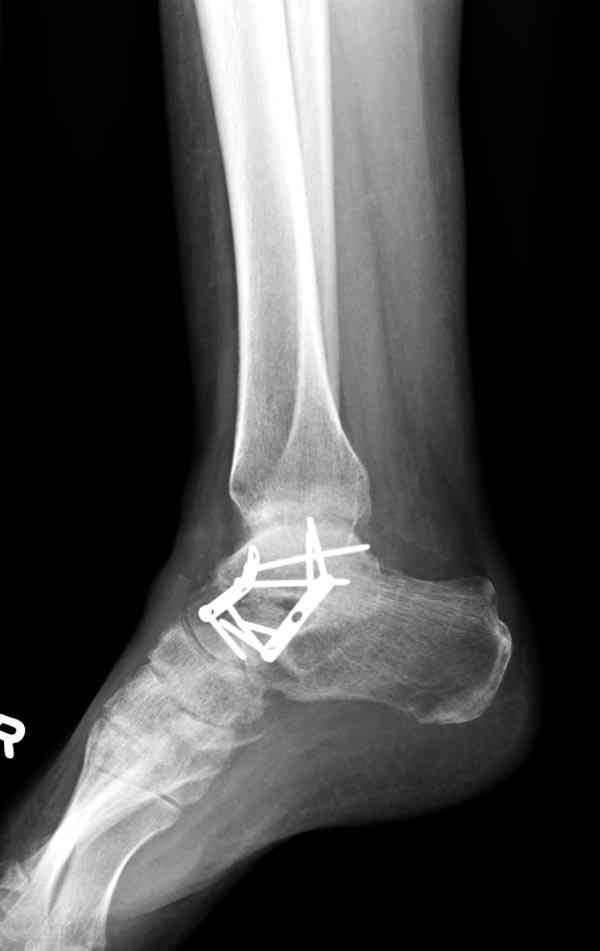

Случай с множественным оскольчатым переломом тарана оперированный из двойного доступа.

Через 2 мес.:

Через 8 мес.:

Через 14 мес.: